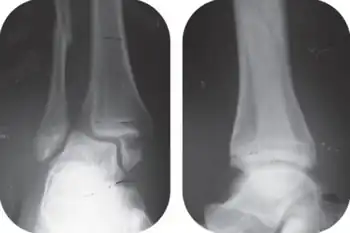

Bimalleolar fracture

A bimalleolar fracture is a fracture of the ankle that involves the lateral malleolus and the medial malleolus. Studies have shown[1] that bimalleolar fractures are more common in women, people over 60 years of age, and patients with existing comorbidities.[1]